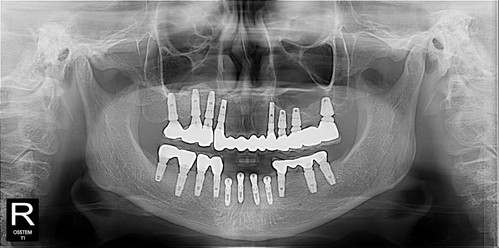

"자면서 안 했으면 나 못했어. 자니까 수술 받았지"

편안히 수술 받으셨으면 됐죠^^

이제 앞니 보철 할 때까지 기다리시기만하면 됩니다.~